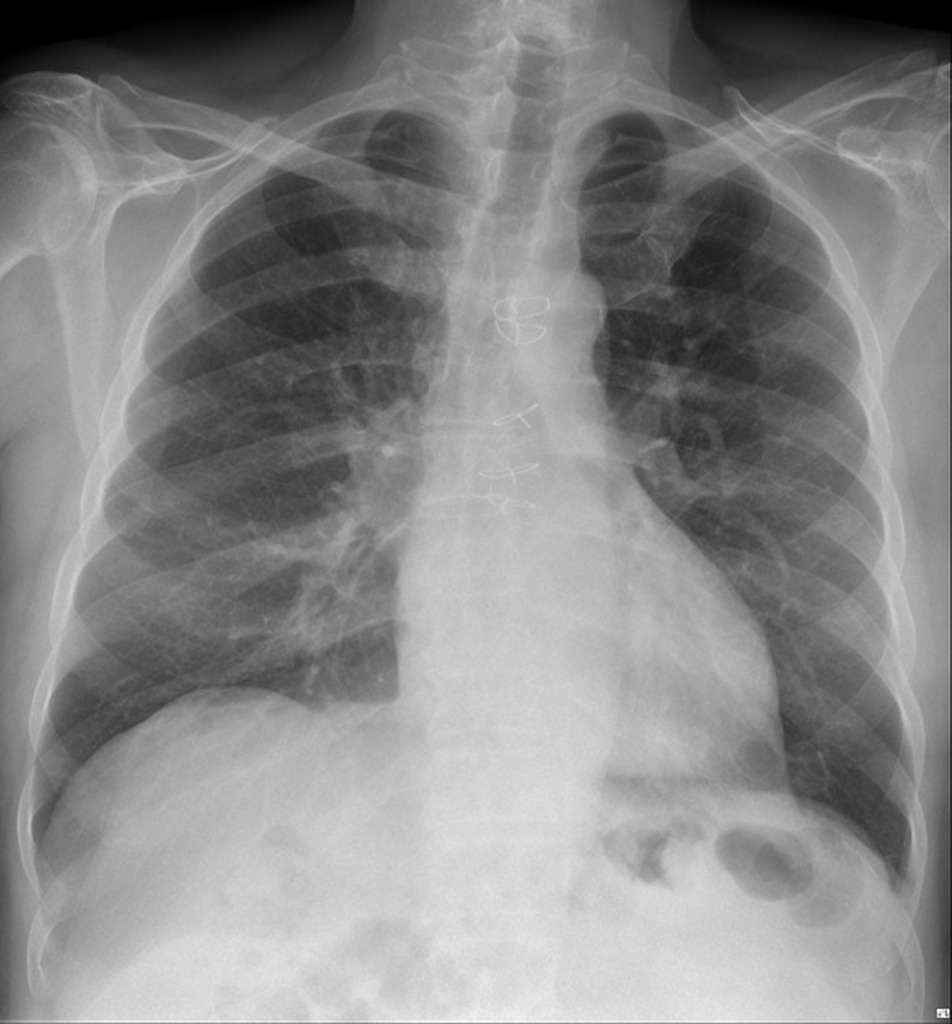

Example 1

Take a look at the following example. Let us go through how we would systematically analyse this and the diagnosis.

“On initial inspection, there appears to be a foreign object in the upper left chest, but I will proceed to go through it systematically.”

A – Starting with the airways, the trachea is not deviated, and the carina is visible.

B – The pleural markings go all the way to the costal margin so there is no evidence of a pneumothorax. Going through the lung zones, there is no opacification.

C – The heart is not enlarged and there is no loss of the heart border.

D – The hemidiaphragms are clearly visible and there is no blunting of the costophrenic angles. There is no free air under the diaphragm.

E – There is a pacemaker present, situated under the left clavicle. There are 2 wires which attach to the right atrium and the left ventricle.

There is no abnormality in the review areas, including the apices, behind the heart.

In summary the key finding is that there’s a pacemaker in situ

Pacemaker